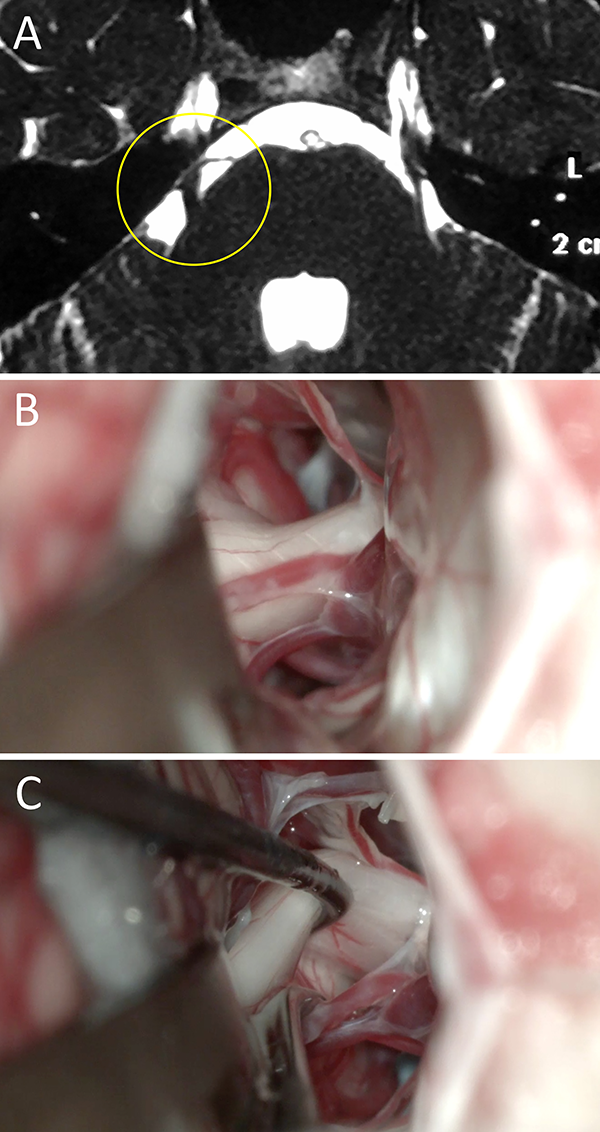

Figura 2:

Varón de 45 años de edad con clínica de NT típica refractaria al tratamiento farmacológico. En RM no se evidencio CNV alguno, por esto su neurólogo de cabecera indicó tratamiento farmacológico durante más de un año. Finalmente consultó con nuestro equipo y se decidió conducta quirúrgica en virtud a la clínica. En el intraoperatorio se evidenció un claro CNV del lado izquierdo. Evolucionó favorablemente con remisión del cuadro doloroso. A) RM preoperatoria; B) hallazgo intraoperatorio, CNV ; C) colocación de teflón. NT: neuralgia trigeminal; RM: resonancia magnética; CNV: conflicto neurovascular.